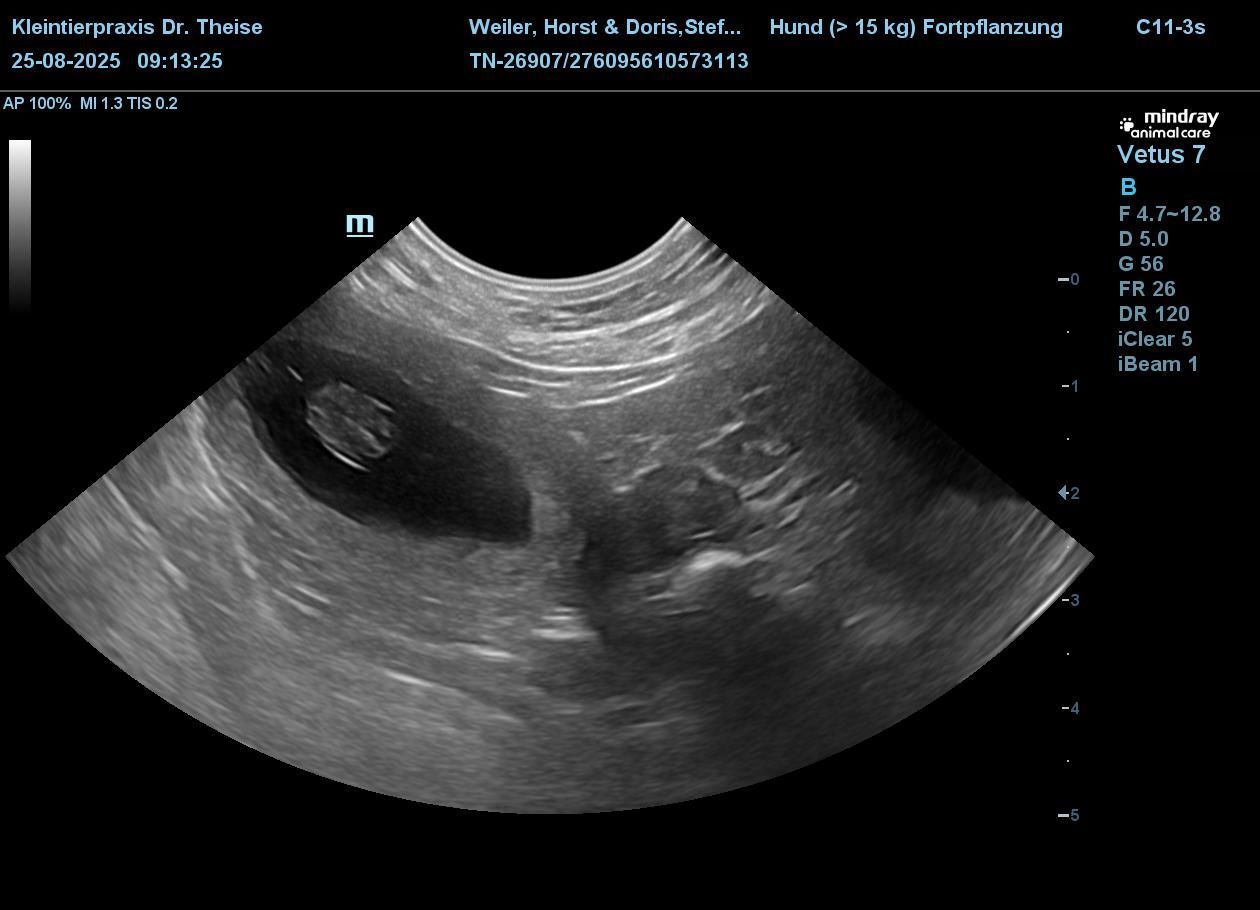

Wir sind so glücklich, Fleur ist belegt. Beim Ultraschall wurden 6 Welpen gezählt.